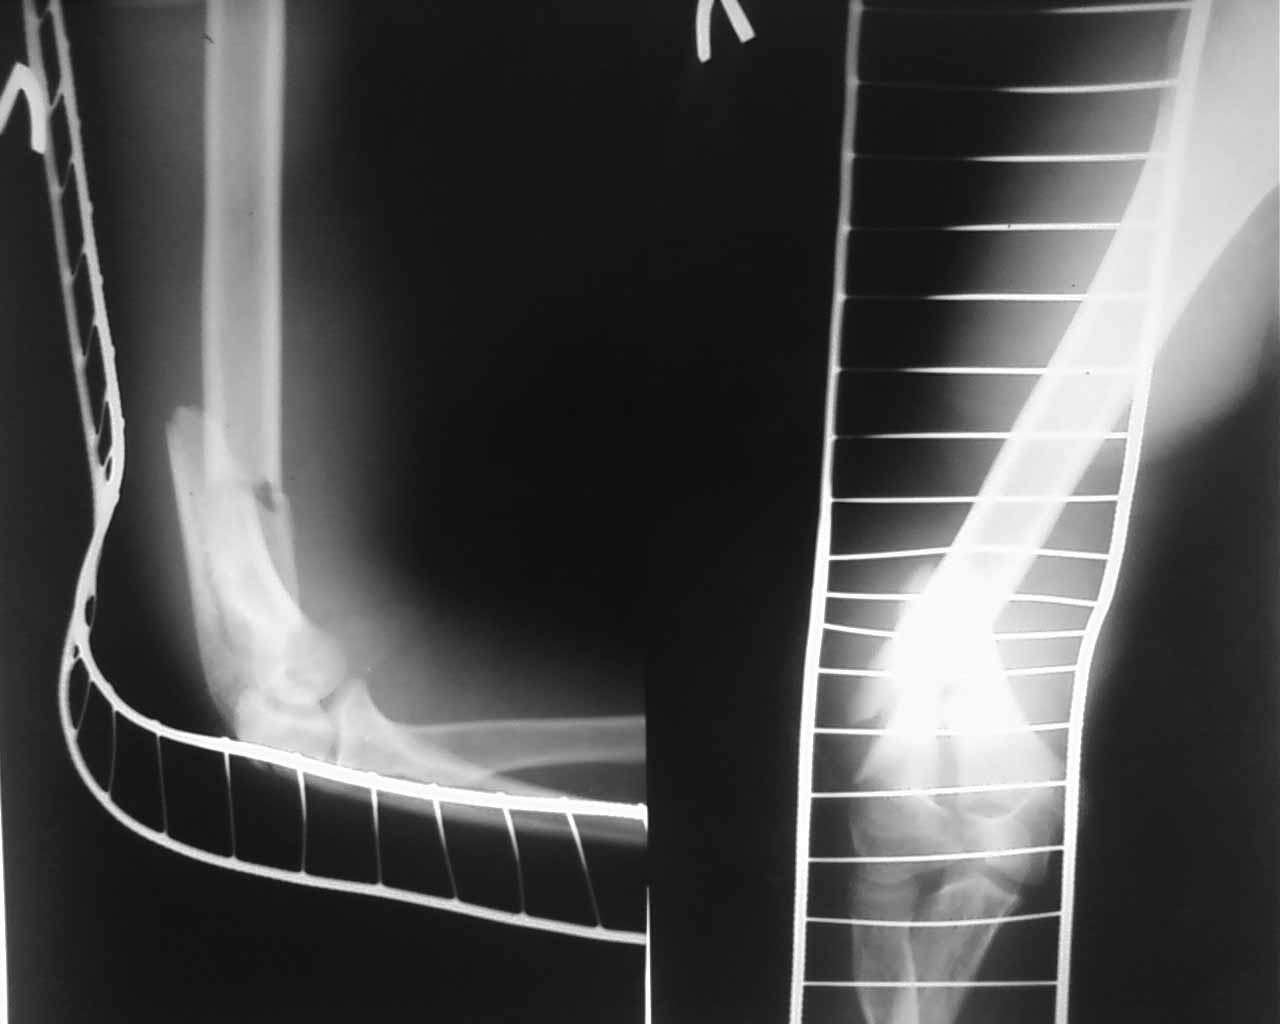

открытый т- образныйй внутрисуставной перелом дистального метаэпифиза плеча у ребёнка 13 лет |

Уважаемые коллеги! Помогите подобрать оптимальную методику лечения больного. В отделение травматологии и ортопедии поступил подросток 13 лет за 2 часа получил травму- упал с велосипеда на левую руку. В ЦРБ по месту жительства наложена гипсовая повязка. DS Открытый внутрисуставной Т- образный межемыщелковый перелом дистального отдела плечевой кости со смещением. Снимки представляю. Безусловно,необходим стабильно- функциональный остеосинтез- есть мысль-выполнить открыто репозицию задним доступом, стягивающий винт с целью межфрагментарной компрессии мыщелков, предварительная фиксация спицами, далее перейти к внеочаговой фиксации АНФ- спице- стержневым модулем. Погружной остеосинтез , думаю не целесообразен , поскольку это ещё ребёнок ( зоны роста) , открытый перелом тоже в пользу внешней фиксации. Подскажите оптимальный вариант с учётом возраста больного.Буду очень признателен.